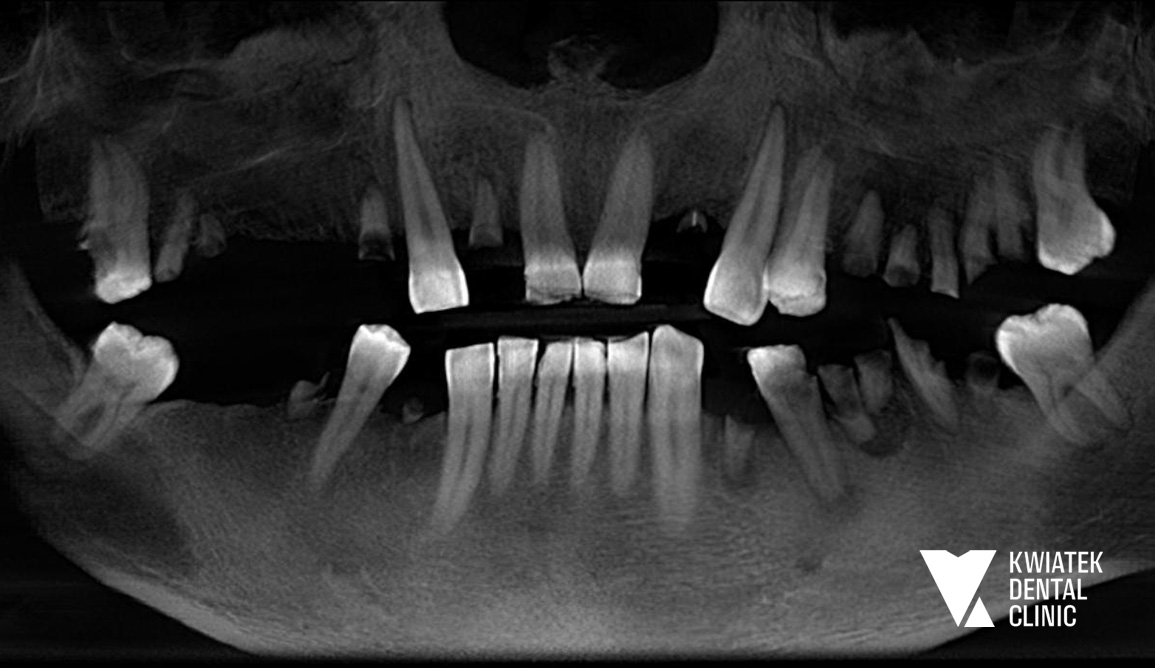

PRZED

Pacjent zgłosił się do naszej Kliniki z potrzebą całościowego przywrócenia funkcji i estetyki uzębienia. Leczenie rozpoczęliśmy od profesjonalnej higienizacji, aby usunąć złogi nazębne oraz płytkę bakteryjną, co stworzyło prawidłowe warunki do dalszych zabiegów.

Następnie wykonano leczenie endodontyczne (kanałowe) zębów kwalifikujących się do odbudowy protetycznej, eliminując przy tym stany zapalne.

W kolejnym etapie usunięto ósemki, a po wygojeniu tkanek wykonano skany cyfrowe i rejestrację zwarcia, aby precyzyjnie zaplanować rozmieszczenie implantów i kształt przyszłych koron. Podczas zabiegów zastosowano szablony chirurgiczne, co pozwoliło bezpiecznie i precyzyjnie wszczepić implanty zębowe.